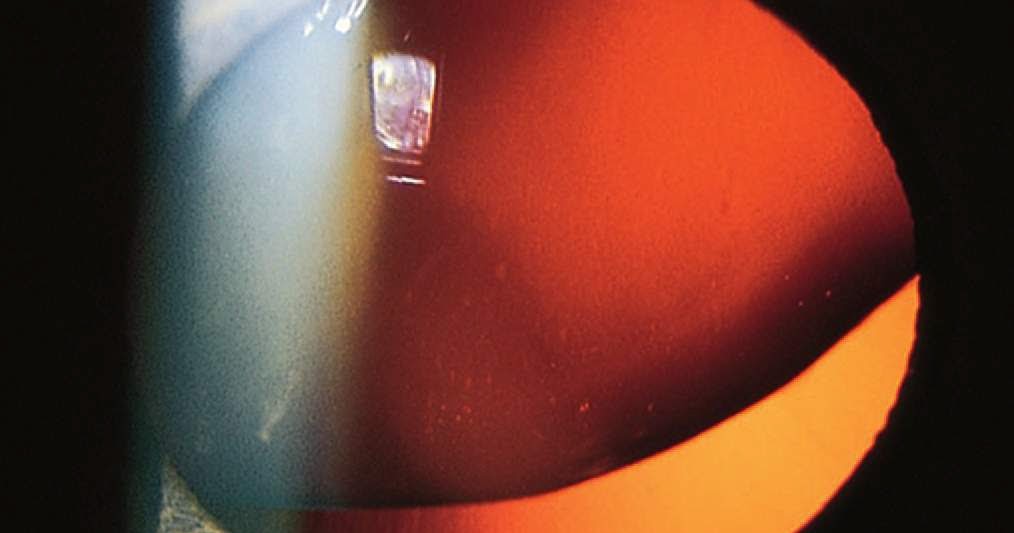

Ophtnotes Hydrodissection separates the lens from the...

Ophtnotes Hydrodissection separates the lens from the... Is The Lens Capsule Removed During Hydrodissection The aim of the hydrodissection step is to break adhesion between the inside of the lens capsule and the outermost cortical layer of the lens. The lesser the adhesion between the lens and capsular, the safer and more effective is the rotation and removal of the lens, especially. After the injection of fluid beneath the anterior capsule, the capsule is. Is The Lens Capsule Removed During Hydrodissection.